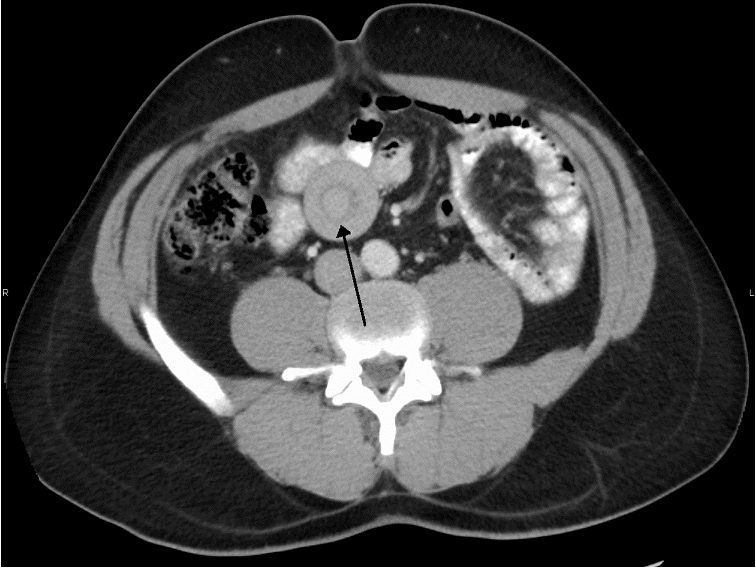

Abdominal CT: Perform if ultrasound and abdominal x-ray are inconclusive.

Colosigmoidal intussusception in a 4-year-old girl